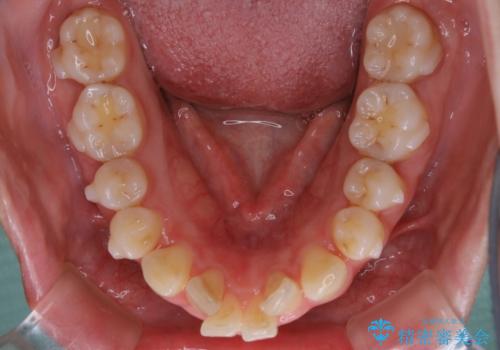

- 歯のガタつきと口元の突出感を主訴に来院されました。

装置の希望がインビザラインだったため、非抜歯でインビザラインの特徴を最大限に生かして行う矯正治療を選択しました。

一般的に口元を下げるための治療というと抜歯矯正を思い浮かべる方が多いかと思います。そもそもガタつきを治したり歯を引っ込めるためのスペースの作り方には大きく分けて4種類の方法があります。

①抜歯 ②歯列の幅の拡大 ③IPR(歯の幅を削って小さくする) ④歯の後方移動 です。

インビザラインの登場により抜歯以外の3種類の方法を効率よく活用することができるようになりました。

そのため、非抜歯でも口元の環境が改善するケースがあります。